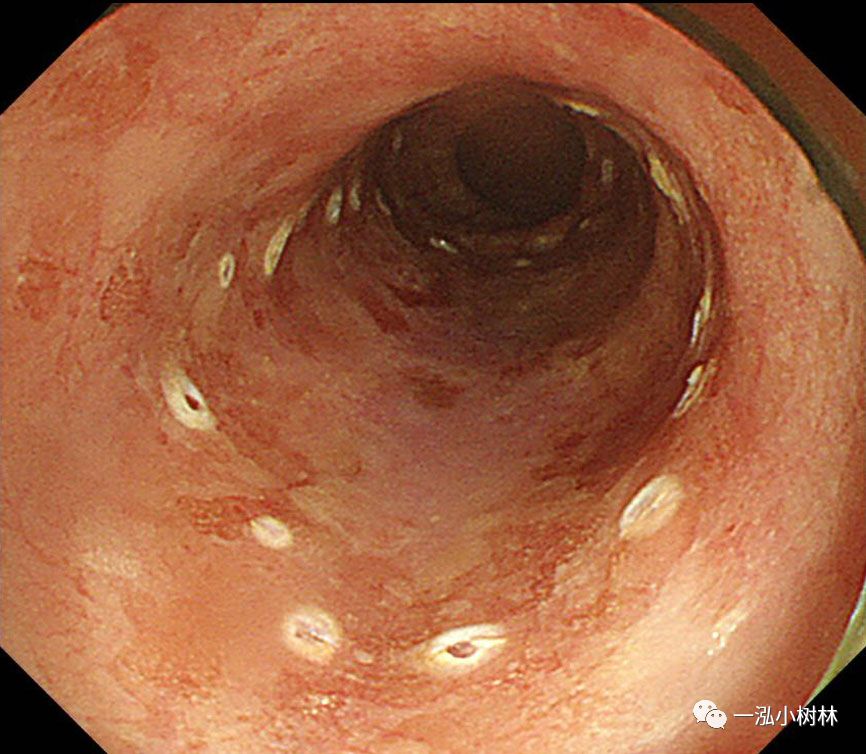

图2 NBI:病变呈褐色(BA)